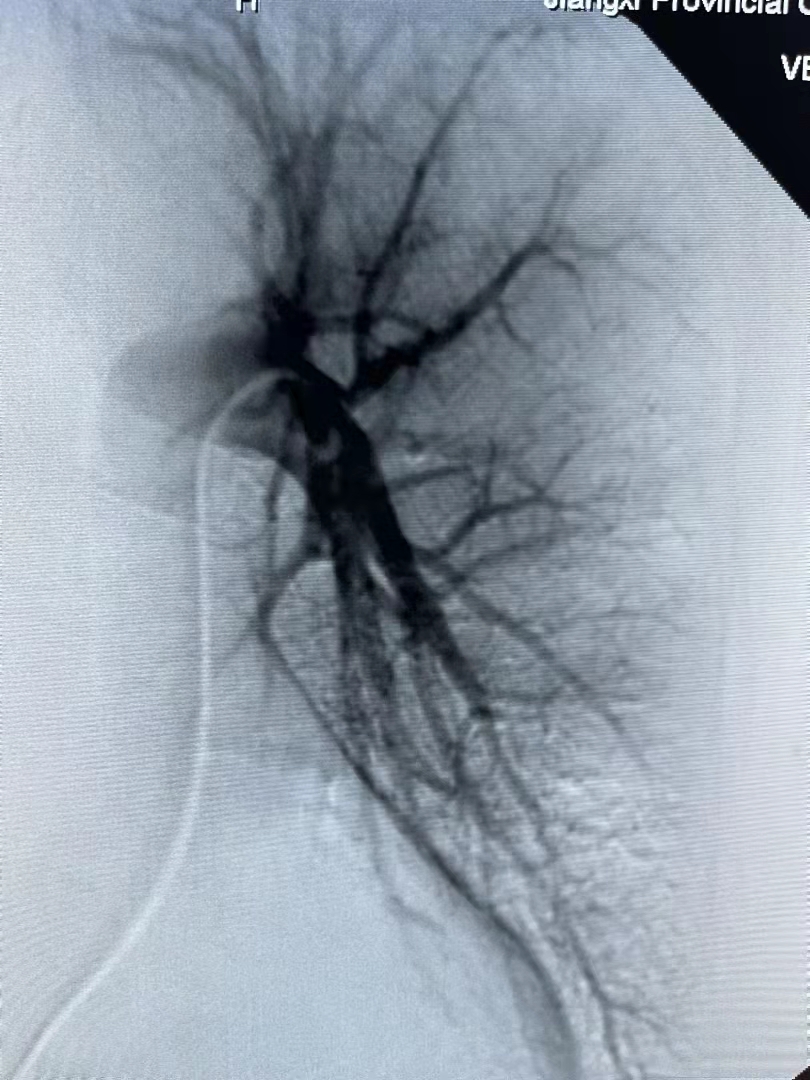

近日,門診收治了一位咯血的老奶奶到介入血管科。時逢周六,醫(yī)生出于安全考慮立即安排增強CT,檢查提示肺隔離癥。這一較為少見的先天性疾病,既往治療以外科手術(shù)切除病變組織為主,考慮到患者年紀大,外科手術(shù)風(fēng)險大,介入血管科團隊經(jīng)慎重考慮予以實施血管栓塞術(shù)。在局麻下經(jīng)股動脈穿刺引入導(dǎo)管與導(dǎo)絲,導(dǎo)管與導(dǎo)絲配合插管至肺隔離癥的供血動脈內(nèi),經(jīng)造影證實屬于肺隔離癥的供血動脈后,選擇直徑大于各分支動脈20%的金屬彈簧圈,對其進行徹底栓塞。經(jīng)過一個多小時的奮戰(zhàn),終于順利完成手術(shù)。